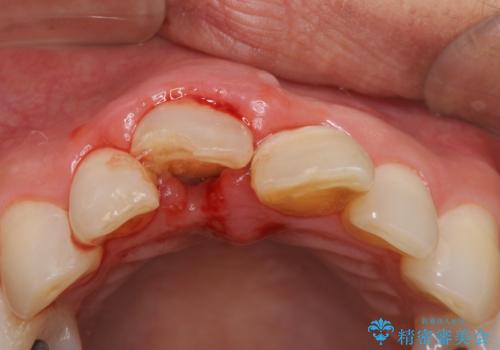

検査の結果、歯は大きく折れておらず、骨の中に埋め込まれていた状態であったため、部分矯正で歯を引っ張り出していきます。

ぶつけて埋まってしまった歯は、場合によって矯正治療で引っ張り出すことで保存することができます。

今回は歯の神経が死んでしまっていたため、根管治療後に被せ物を装着して見た目の綺麗さを回復しました。